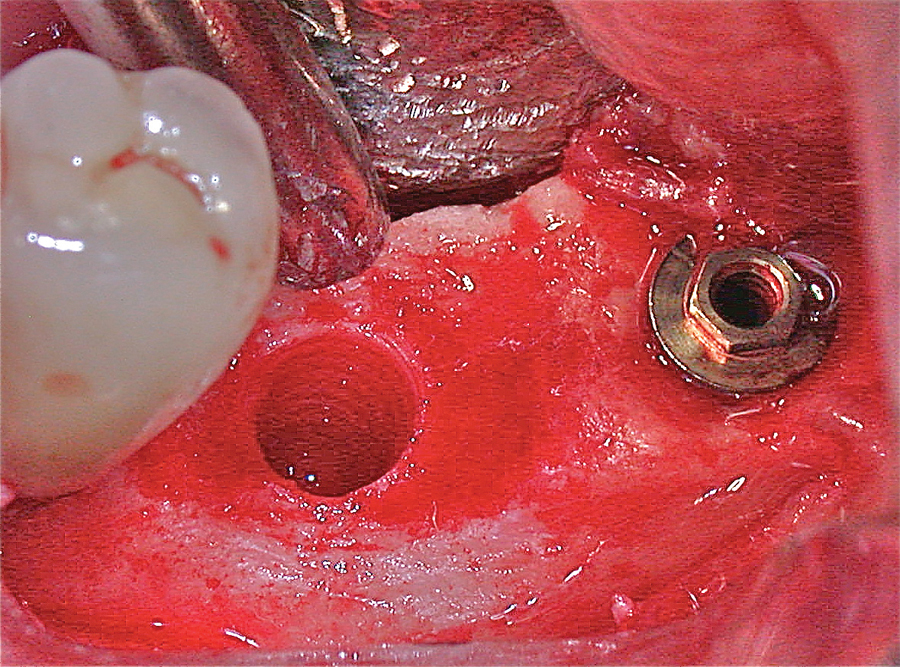

The success of a delicate periodontal procedure is dependent on both the skill of the clinician as well as several patient-associated factors. These include the past and present smoking status, systemic health conditions and compliance to post-operative protocols. Any one of the factors or in combination can delay or impair the healing process. However, common … Read more